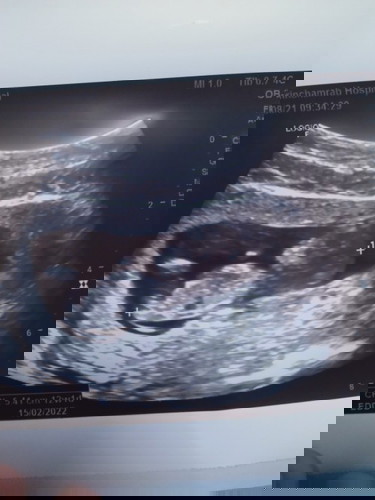

หนูได้12สัปดาห์แล้ว แพ้หนักมากเหม็นทุกอย่างเลย จะได้ลูกชายหรือลูกสาวค่ะ ขอบคุณสำหรับคำล่วงหน้าค่ะ

อยากรู้ว่าน้องเพศชายหรือหญิงค่ะ

รออีกสัก 4สัปดาห์ น่าจะเริ่มเห็นเพศแล้ว แพ้น้อยแพ้มากบอกเพศไม่ได้เลยค่ะ